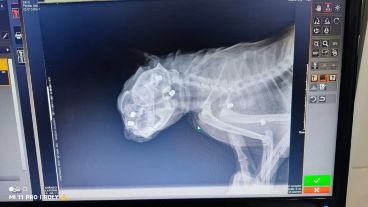

El hecho tuvo lugar en la zona de Cazadores al 2700. La gatita tuvo que ser atendida y los veterinarios no podían creer la brutalidad del ataque sufrido: la placa evidencia claramente los 6 impactos, 4 en el cráneo y los restantes en la parte del abdomen.